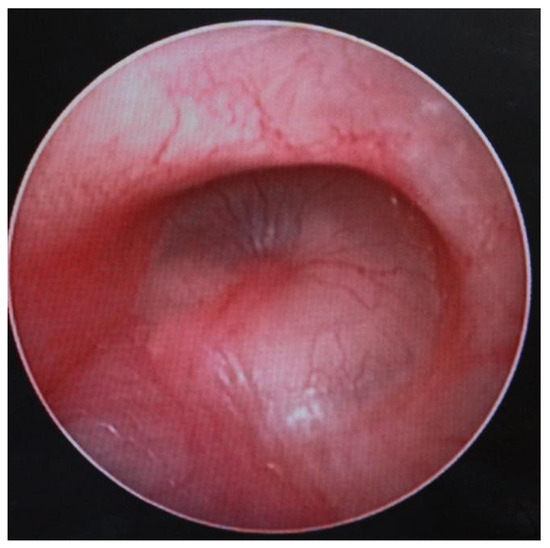

3.1.2. Computed Tomography and Magnetic Resonance Imaging